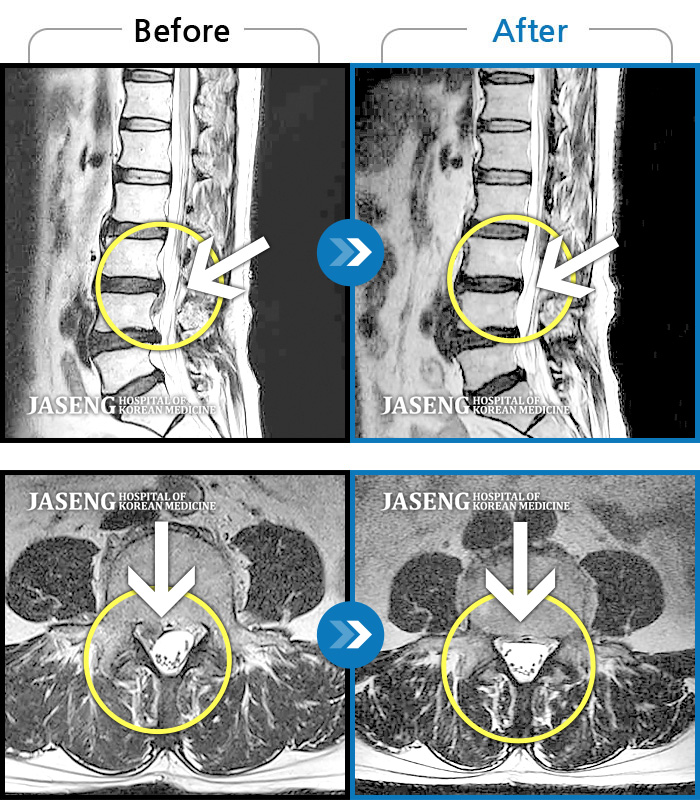

허리디스크

안산 · 김민수 원장

어떤 자세에도 통증이 지속되었다.

촬영시기

2018.10.25 ~ 2024.06.19

2024.07.31